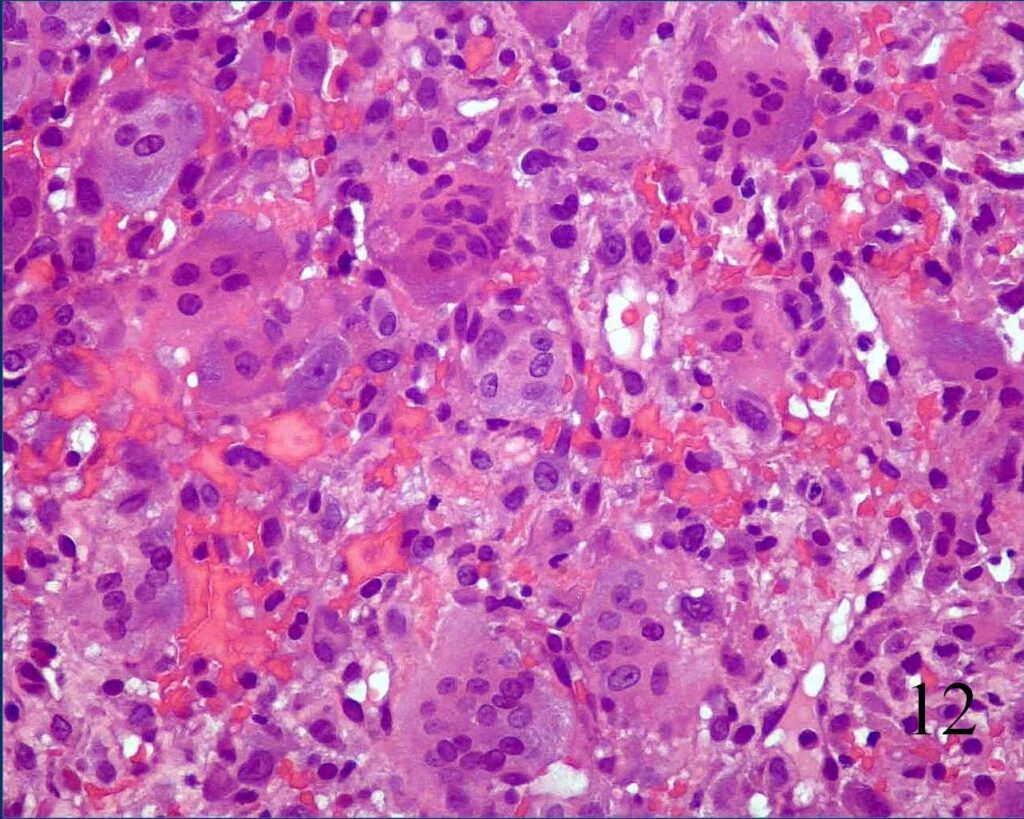

· On high power magnification, the nuclei of the giant cells and nuclei of the mononuclear background cells are similar. (Fig. 12)

- Mitotic figures but normal appearance and no atypical mitoses.

Fig. 12 Microscopic: High power magnification shows many multinucleated giant cells surrounded by a sea of mononuclear cells. The nuclei in the mononuclear cells appear very similar to the nuclei in the giant cells. There are mitotic figures but no abnormal mitoses.